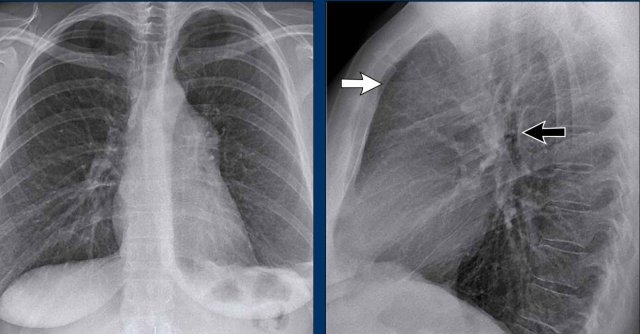

Mediastinal Masses on Lateral View

When the superior mediastinum appears widened on the PA view, the lateral view is useful to localize the abnormality.

• A soft tissue density in the retrosternal space narrows the differential diagnosis to anterior mediastinal masses, commonly remembered as the "4 Ts":

• Thymoma

• Teratoma (germ cell tumors)

• Thyroid mass

• Terrible lymphoma

In this case, the patient was diagnosed with Hodgkin lymphoma.